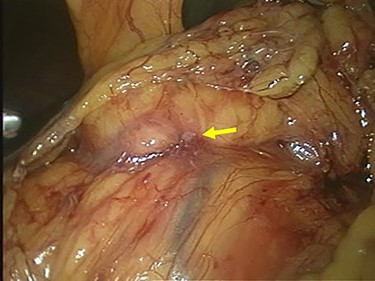

Staging laparoscopy showed no peritoneal dissemination or liver metastasis, but direct invasion of the gastric tumor to the pancreatic head was revealed (Fig. 5). The clinical diagnosis was cT4N(+)M0 StageIVA according to the TNM Classification of Malignant Tumors, 8th Edition. We decided to start chemotherapy to shrink the tumor and cause it to separate from the pancreatic head.

Laparoscopic finding showed that there was no peritoneal dissemination or liver metastasis, but the direct invasion of the gastric tumor to the pancreatic head was suspected (arrow).